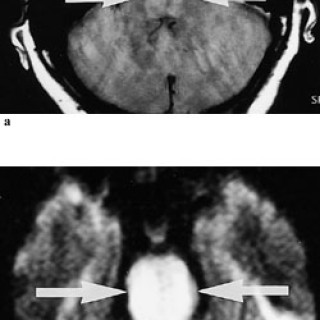

Gassemboli kan oppstå som følge av kirurgi, diagnostiske prosedyrer, traumer, lungeskader, bruk av hjerte-lunge-maskin og ved trykkfallssyke (1, 2). Gassemboli er en sjelden komplikasjon, men kan resultere i betydelig morbiditet, i verste fall død. Det er grunn til å tro at særlig iatrogen gassemboli i liten grad blir erkjent. Det er viktig at leger og sykepleiere i større grad blir oppmerksom på problemet, da de fleste pasientene vil kunne unngå sekvele med adekvat behandling. Med gassemboli menes vanligvis luftemboli, men med dagens bruk av andre gasser i medisinsk øyemed kan eksempelvis...